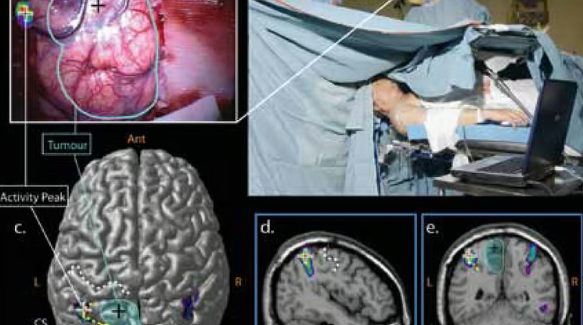

Patient remains awake to monitor vital functions, allowing safe tumor removal near critical brain areas.